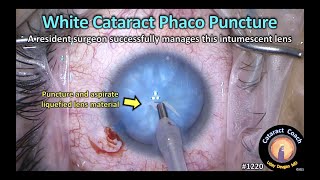

HIGLY EFFECTIVE & SAFE TIPS TO DEAL WITH INTUMESCENT CATARACT-WITH SUBTITLES CataractCoach 1220: intumescent white cataract phaco puncture

CataractCoach 1220: intumescent white cataract phaco puncture Capsulorhexis in intumescent cataract - 2 stage technique 2017 (HD)

HIGLY EFFECTIVE & SAFE TIPS TO DEAL WITH INTUMESCENT CATARACT-WITH SUBTITLES CataractCoach 1220: intumescent white cataract phaco puncture

CataractCoach 1220: intumescent white cataract phaco puncture Capsulorhexis in intumescent cataract - 2 stage technique 2017 (HD)